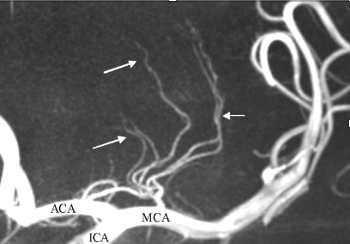

Which arteries do the arrows point to? [1]

A

Lenticulostiate arteries

How well did you know this?

226